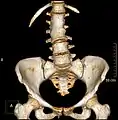

Congenital block vertebra of the lumbar spine. CT volume rendering.

3D image of a lumbar vertebra